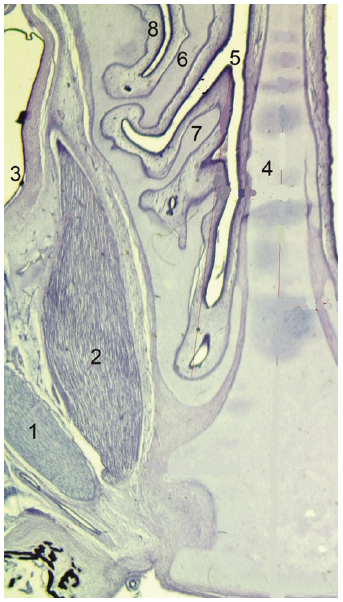

В пренатальном периоде онтогенеза человека носовая полость отделена от глазницы тонкой пластинкой решетчатой кости (рисунок 2).

Рисунок 2. Взаимоотношение верхнего носового хода и глазницы: 1 – латеральная прямая мышца глаза, 2 – медиальная прямая мышца глаза, 3 – глазное яблоко, 4 – перегородка носа, 5 – верхний носовой ход, 6 – средняя носовая раковина, 7 – верхняя носовая раковина, 8 – средний носовой ход.

Figure 2. The relationship of the upper nasal passage and orbit: 1 – the lateral rectus muscle, 2 – the medial rectus muscle, 3 – eyeball, 4 – nasal septum, 5 – superior nasal meatus, 6 – middle nasal concha, 7 – superior nasal concha, 8 – middle nasal meatus.

Примечание. Горизонтальная гистотопограмма. Окраска гематоксилином и эозином. Фото под микроскопом MicroOptix MX 1150, ок.10х/22мм., об.1. Протокол №9, плод, 16 нед., жен.

На горизонтальных гистотопограммах в начале исследуемого периода – в 14 недель гестации – в общий носовой ход выступают носовые раковины. Указанные сроки согласуются с данными Е.Н. Миновой [16]: «…к 15–16 неделям гестации уже хорошо сформированы нижняя, средняя и верхняя носовые раковины». Согласно исследованиям К.К. Баранова [17], уже в 8 недель развития зачатки носовых раковин принимают свое окончательное положение, а в срок 17–18 недель начинаются процессы оссификации предшественника нижней носовой раковины.

Как видно из рисунка 2, верхняя и средняя носовые раковины исходят от решетчатой кости, в своем начальном отделе имеют сужение, постепенно расширяются и приобретают каплевидную форму. Носовые раковины покрыты со всех сторон слизистой оболочкой. Верхняя носовая раковина короткая, узкая, в своем свободном отделе имеет заострение. Средняя носовая раковина более массивна, частично перекрывает носовой ход. Согласно Н.Б. Кузняк [18], средняя носовая раковина в носовом ходе направлена вниз и медиально, в 12 недель имеет переднезадний размер 4,50 мм. В промежуточном плодном периоде онтогенеза переднезадний размер правой средней носовой раковины составил 12,35±3,76 мм (при диапазоне колебаний от 4,05 до 17,10 мм). Переднезадний размер левой средней носовой раковины составил 11,96±3,69 мм (при вариативном диапазоне от 2,95 до 16,96 мм). На диаграмме 1 проведен сравнительный анализ переднезаднего размера средней носовой раковины у плодов мужского и женского пола.